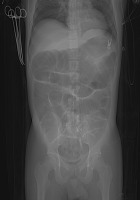

A 28-year-old man was admitted to hospital due to acute pancreatitis after alcohol abuse. The patient was given antibiotic treatment (amoxycillin/clavulanic acid) in the surgery department and after three days of hospitalization deteriorated due to systemic inflammatory response syndrome (SAPS II 21, SOFA 8) and was admitted to the ICU. The patient was started with noninvasive ventilation and supportive treatment. The antibiotic was stopped due to lack of signs and symptoms of systemic infection. Because the patient had diarrhea, C. difficile infection was suspected and confirmed with stool examination (positive toxin A and B). Antibiotics were given for severe infection (vancomycin 4 × 125 mg p.o. and metronidazole 3 × 500 mg i.v.). The patient remained in a severe condition mainly because of respiratory failure and paralytic ileus. CT scan of the abdomen showed severe intestinitis without pancreatic necrosis. Antibiotics were continued for 10 days and vancomycin 4 × 500 mg per rectum was started for complicated infection. Simultaneously supportive treatment was continued (mechanical ventilation, catecholamines, fluids and feeding). The patient improved (SOFA 2) and diarrhea stopped. After 7 days of antibiotic withdrawal, diarrhea reappeared and recurrent C. difficile infection was diagnosed. The antibiotics used in primary clostridium infection were introduced. After 4 days of renewed treatment the patient’s condition deteriorated, he developed fever, his neurology deteriorated as well as cardio-respiratory function (SOFA 9). Septic shock was diagnosed due to Escherichia coli infection with the point of origin in the intestine. Systemic antibiotics were introduced that led to quick progression of C. difficile infection. Paralytic ileus dominated in the clinical picture. CT scan of the abdomen showed toxic megacolon (Figure 1). Radical surgical intervention such as colectomy was considered, but eventually abandoned. The surgical team decided that the patient did not have any chance of survival and such a radical operation would not be beneficial. Emergency cecostomy was performed because of high intraabdominal pressure (IAP – 19 mm Hg) leading to acute renal failure requiring CRRT. After 10 days of ineffective treatment with antibiotics the patient was qualified for emergency fecal microbiota transplantation. We used unrelated donor fecal microbiota from a fecal microbiota transplantation (FMT) bank in the Medical University of Gdansk. In the course of preparation for transplantation vancomycin and metronidazole were stopped and systemic antibiotics for enteric sepsis were continued. It was difficult to decide which way to administer the prepared fecal microbiota. Administration through a nasogastric tube was virtually impossible due to gastroparesis, risk of regurgitation and ineffective transport through the pylorus. Colonoscopy was difficult to perform because the bowel could not be properly prepared and there was a risk of bowel perforation. We decided to inject 200 mL of prepared microbiota through cecostomy with a 100 mL syringe via a Foley catheter. Shortly after transplantation the patient still had fever, white blood cell count increased and the circumference of the abdomen increased due to bowel gas production. IAP transiently increased to 35 mm Hg and then started to decrease with subsequent peristalsis improvement. Normalization of IAP led to hemodynamic improvement (Figure 2) and return of adequate renal function (Figure 3). Two additional fecal microbiota transplantations were performed after 7 and 10 days. After every transplantation there was a transient inflammatory response with subsequent IAP reduction. After 65 days of ICU treatment the patient was transferred to a gastroenterology department.

FIGURE 2

Norepinephrine dose reduction as a result of hemodynamic improvement after fecal microbiota transplantation